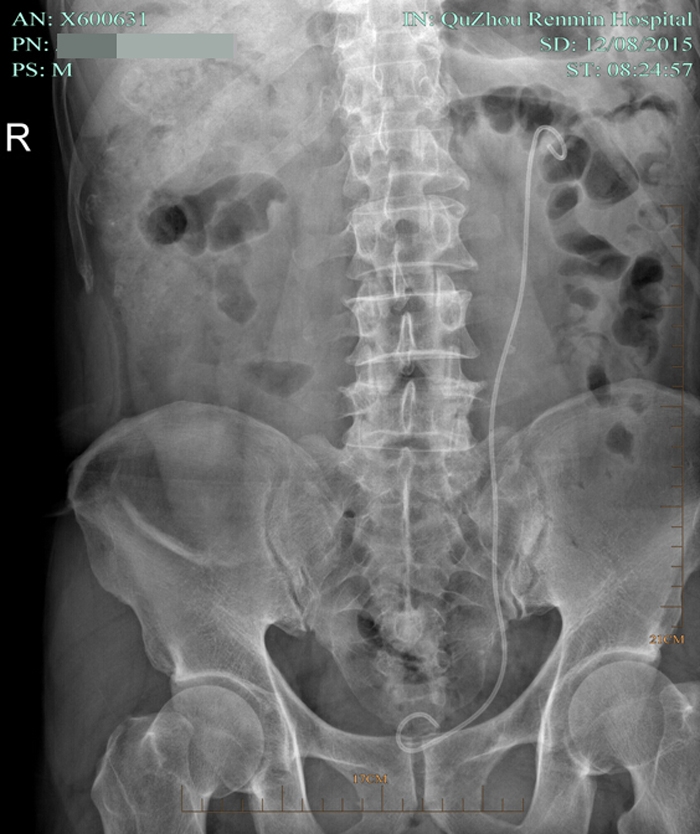

??? 術(shù)后第七天,復(fù)查泌尿系平片無結(jié)石殘留,拔了腎造瘺管出院。因為腎結(jié)石手術(shù)都需要放置輸尿管支架管,出院時護(hù)士叮囑出院后要多喝水,避免活動過多引起血尿,1個月后來拔支架管。

術(shù)后復(fù)查平片

術(shù)后復(fù)查泌尿系平片